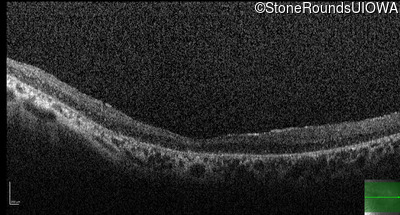

Optical Coherence Tomography - Right - 10/200

Exemplar / OCT Stack